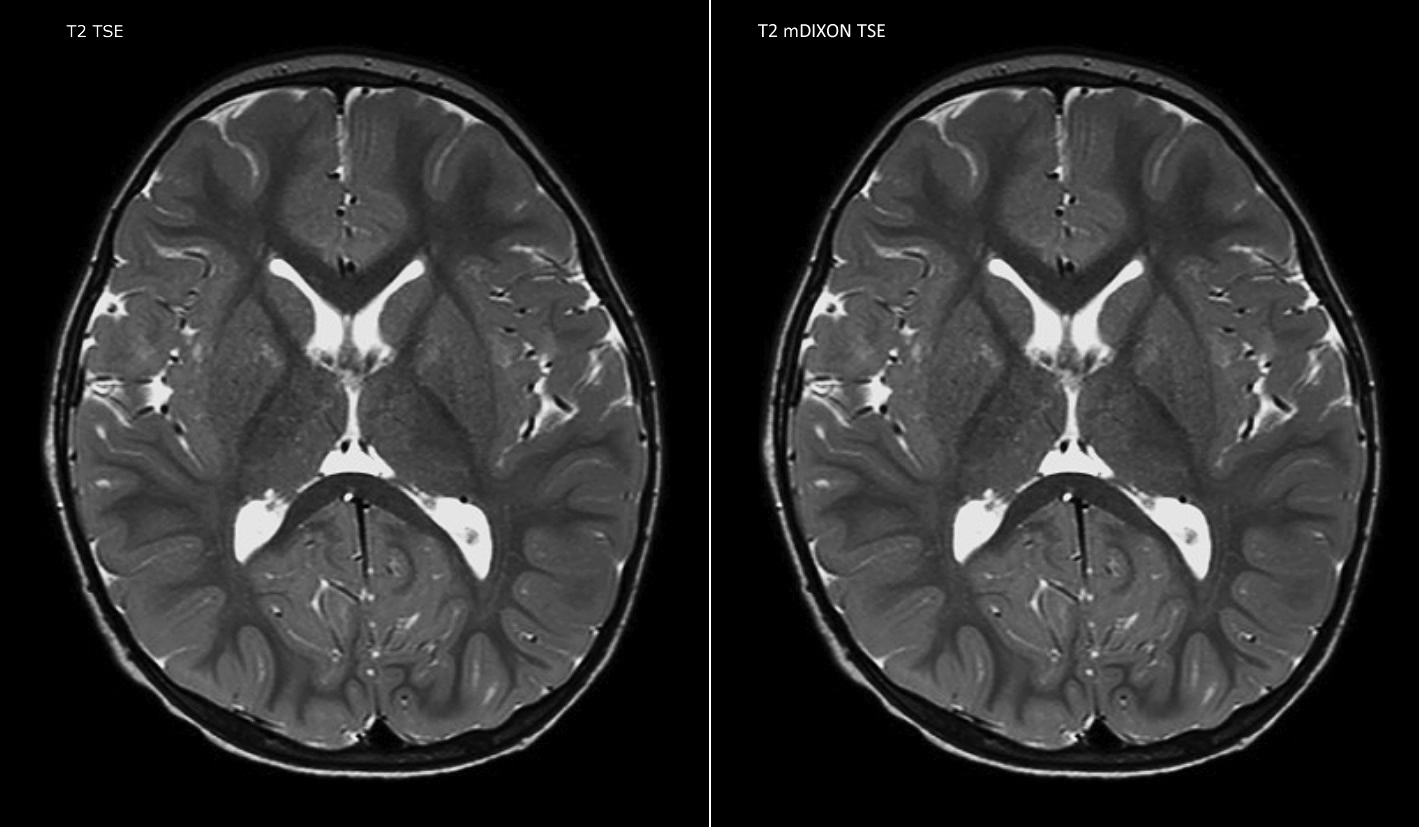

La TSE mDIXON Philips est une technique DIXON à deux points qui sépare les signaux d’eau et de graisse pour une imagerie sans graisse rapide, même dans le domaine complexe de la neuroanatomie. “La TSE mDIXON est l’une des améliorations les plus importantes des séquences d’imagerie que nous utilisions jusqu’alors au PCH”, admet le Dr Miller. “Son acquisition multi-paramétrique nous permet d’obtenir dans la même séquence des images avec suppression de graisse et les images T2 équivalentes sans suppression de graisse. En outre, les anciennes méthodes de suppression de graisse pouvaient être corrompues artificiellement par une anatomie inhabituelle du patient ou par une mauvaise application de l’opérateur. Avec mDIXON, nous disposons désormais d’une méthode efficace et fiable pour supprimer la graisse.” La saturation de la graisse a toujours été difficile aux extrémités du champ d’acquisition, en particulier dans l’imagerie du rachis total et dans les zones anatomiques difficiles, comme les régions inférieures du cou. “Toutefois, grâce aux capacités uniques de suppression de graisse du mDIXON, ces difficultés ne sont plus valables” affirme le Dr Miller. “Nous obtenons quotidiennement une suppression de graisse homogène dans presque toutes les conditions. Cela nous a également mené à un meilleur rendement puisque nous n’avons plus à répéter les séquences à cause des défaillances techniques.”

“La TSE mDIXON a renforcé la fiabilité de nos diagnostics en nous permettant de garder ou d’écarter les anomalies pour lesquelles la suppression de graisse est essentielle au diagnostic, comme les maladies métastatiques ou les anomalies osseuses.”

“La TSE mDIXON est la technique la plus utile chez les patients atteints de lésions ou d’anomalies des tissus mous, par exemple du visage et du cou, et chez les patients victimes d’anomalies de contraste principalement visibles avec la suppression de graisse”, indique le Dr Miller. “Toutes nos imageries du rachis contiennent désormais des images T2 mDIXON avec eau uniquement, ce qui nous permet d’identifier les pathologies potentiellement obscurcies par l’imagerie sans suppression de graisse comme les lésions osseuses. Par ailleurs, il n’est pas nécessaire d’acquérir des images TSE T2 standard supplémentaires car les images mDIXON en phase sont équivalentes aux images TSE T2 standard.”